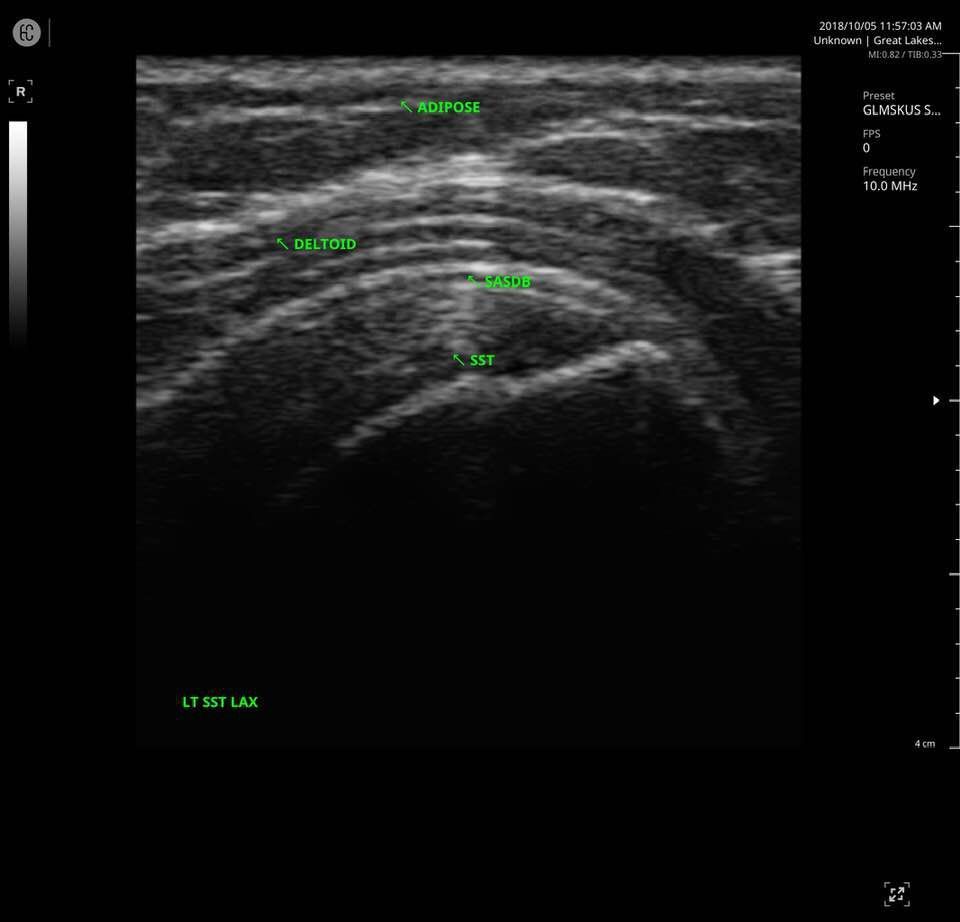

The SONON 300L transducer has cutting-edge technology and its software, combined with a proprietary sensor, turns any mobile device into a mobile ultrasound monitor with the same image quality and knobology as a traditional US machine. Software includes individual preset settings for your most common test.

- MSK

- Multi-frequency: 5MHz 7.5MHz 10MHz